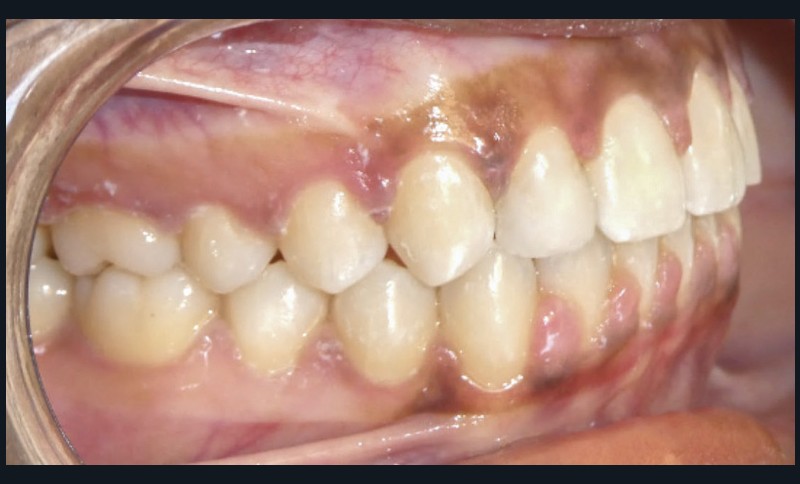

Diagnostic (fig. 1 et 2)

À l’examen extra-oral, la patiente présente un profil biprognathe associé à une Classe II squelettique modérée dans un contexte de normodivergence. L’angle naso-labial apparaît ouvert, le sillon labio-mentonnier est marqué et une prochéilie mandibulaire est observée. Le sourire se révèle disharmonieux, avec une faible visibilité des dents maxillaires.

À l’examen intra-oral, les arcades sont paraboliques, la courbe de Spee est normale. On remarque l’absence de la 23 sur l’arcade ainsi que la persistance de la 63. La patiente présente une Classe II partielle molaire et canine subdivision droite, ainsi qu’une insuffisance de recouvrement. Un léger encombrement incisif mandibulaire est présent, ainsi que des diastèmes maxillaires avec une dysmorphie dento-dentaire de 12 et 22.